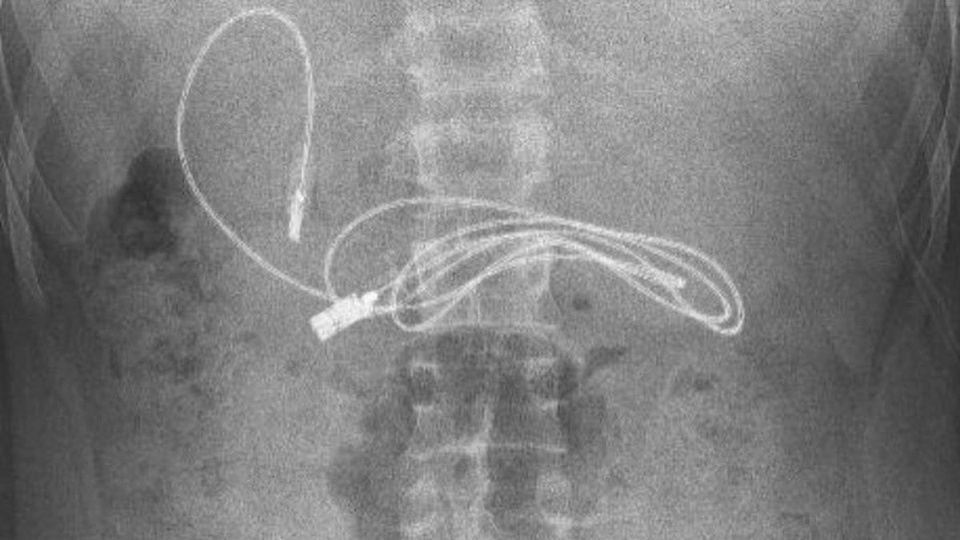

Thiếu niên 15 tuổi nhập viện vì có dây sạc dài gần 1 mét trong dạ dày. Vừa qua các bác sĩ của bệnh viện ở Diyarbakir (Thổ Nhĩ Kỳ) đã chụp X-quang và phát hiện trong dạ dày của bệnh nhân 15 tuổi có đoạn dây sạc dài gần 1 mét.

Kết quả chụp X-quang phát hiện sợi dây sạc trong dạ dày của thiếu niên 15 tuổi. Ảnh: Newsflash.

Cụ thể, tờ New York Post đưa tin một thiếu niên 15 tuổi đã được gia đình đưa đến bệnh viện ở Diyarbakir (Thổ Nhĩ Kỳ) vì buồn nôn và đau bụng.

Sau khi chụp X-quang, bác sĩ phát hiện dạ dày của thiếu niên trên có một thiết bị bọc nhựa đang chờ tiêu hóa. Vì vậy, nhân viên y tế đã đưa bệnh nhân lên xe cấp cứu, chuyển đến Bệnh viện Đại học Firat ở Elazig (cách đó 3 giờ lái xe).

Tại Bệnh viện Đại học Firat ở Elazig, giáo sư Yasar Dogan - Trưởng khoa Tiêu hóa, Gan và Dinh dưỡng nhi - cùng đồng nghiệp đã thực hiện thủ thuật nội soi để loại bỏ dị vật trong dạ dày của bệnh nhân này.

Ngoài sợi dây sạc dài gần 1 mét, các bác sĩ còn lấy ra khỏi dạ dày của bệnh nhân 15 tuổi một dây buộc tóc.

"Chúng tôi đã gặp khó khăn trong việc tháo dây sạc ra, vì một đầu của dây đã đi vào ruột non. Sau khi ca phẫu thuật kết thúc thành công, bệnh nhân đã xuất viện trong tình trạng sức khỏe tốt", bác sĩ Dogan nói.